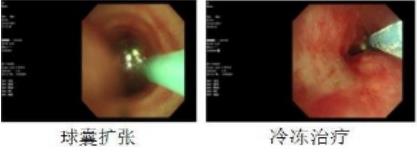

(术前左主支气管明显狭窄,表面见肉芽增生。

球囊扩张、冷冻治疗后,狭窄缓解,管腔通畅)